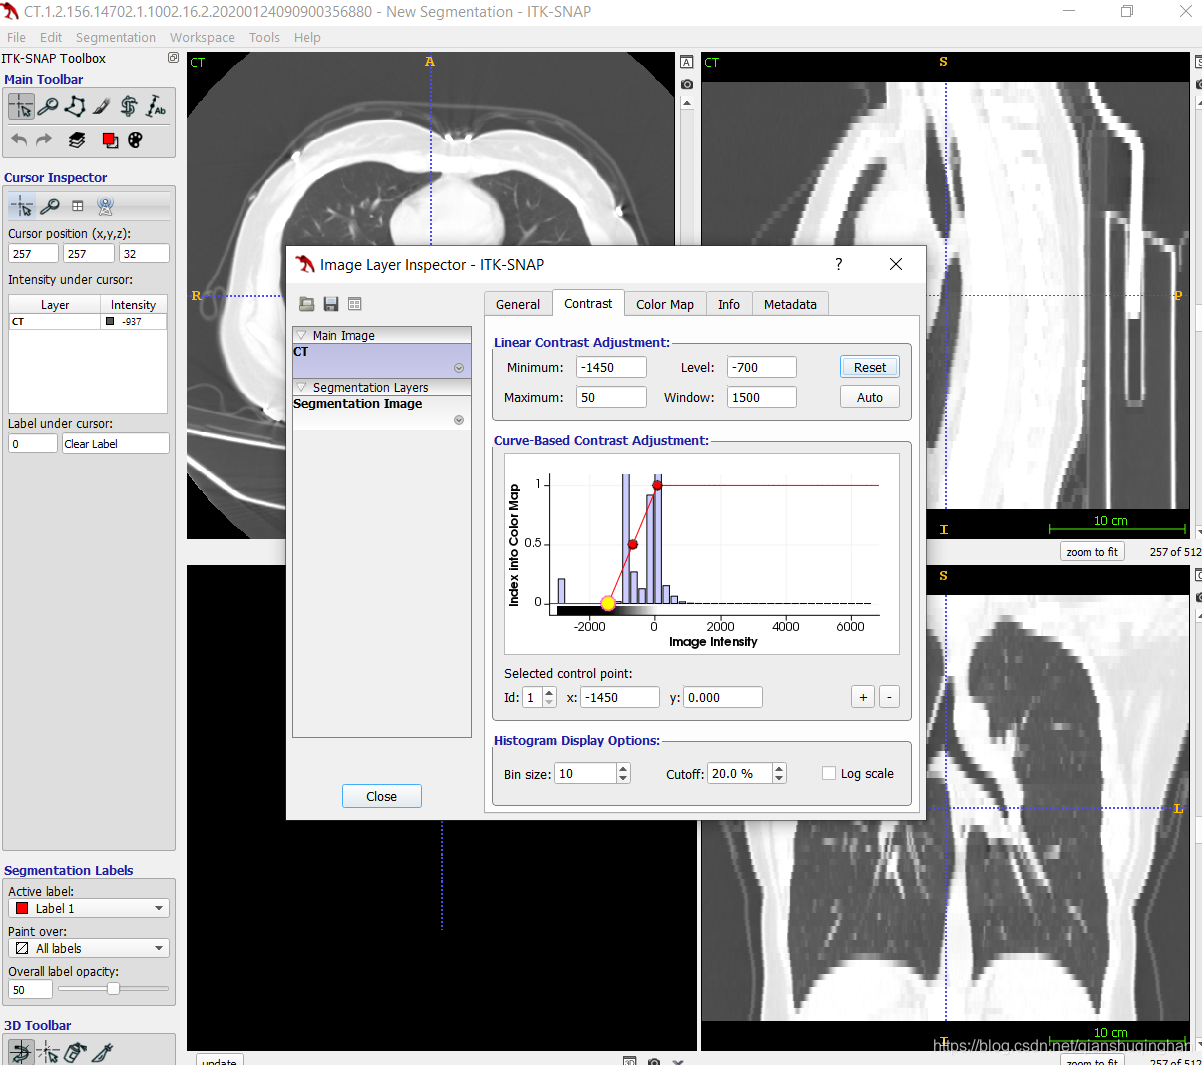

菜单栏:Tools->Color Map Editor, 调整图像窗宽窗位,如肺炎CT可调整为-700/1500, 脑梗死可调整为40/100.